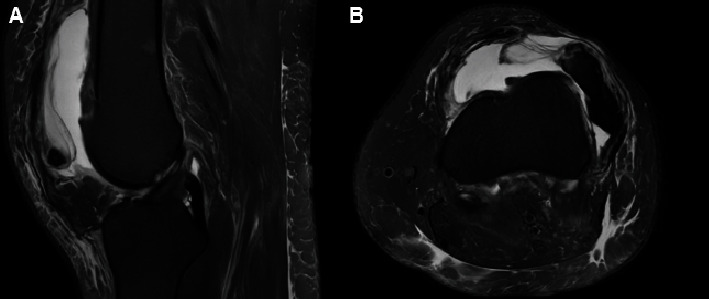

The following case report demonstrates a case of a chronic irreducible patellar dislocation, age-indeterminate associated with a large medial patellar avulsion fracture that was treated with a vastus medialis obliquus advancement following an extensive lateral release. This case is the only known report of this kind in the literature. The patient is a 41-year-old Caucasian female who presented to the clinic with an age-indeterminate, chronically dislocated patella. She has a past medical history of hypertension and ischemic stroke 1 year prior to presentation, leading to expressive aphasia and lower extremity weakness in addition to patellar instability dating back to age 13. An unsuccessful patellofemoral reduction was performed at an outside clinic, and she was placed in a knee immobilizer and referred to our office. Clinically, the patient had limited knee range of motion with a fixed lateral patellar dislocation that was confirmed on imaging. This case report demonstrates a surgical reduction technique that can be utilized by orthopedic surgeons for chronic patellar dislocations that are not amenable to routine patellar instability surgeries due to the contraction of surrounding soft tissue, chronic bone abnormalities, and position of the chronic dislocation. An extensive lateral release followed by vastus medialis obliquus advancement was performed to center the patella within the trochlear groove and to allow for stable articulation throughout range of motion. The patient was able to regain painless, full range of motion of her knee postoperatively with patellar stability noted on both physical exam and radiographic imaging.

Abstract Image